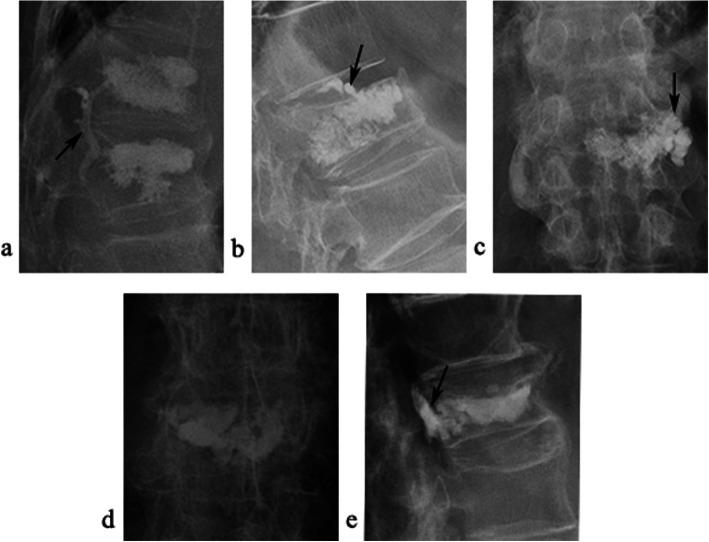

A total of 295 levels of vertebrae were included, with a leakage rate of 32.5%. Univariate analysis showed delayed surgery and lower vertebral compression ratio were the independent risk factors of cement leakage. The stepwise logistic analysis revealed percutaneous vertebroplasty was a risk factor in vein cement leakage; delayed surgery, preoperative compression ratio, and upper endplate disruption were in intradiscal cement leakage; age, preoperative fracture severity, and intravertebral vacuum cleft were in perivertebral soft tissue cement leakage; no factor was in spinal canal cement leakage. The nomogram for intradiscal cement leakage had a precise prediction ability with an original concordance index of 0.75.

Delayed surgery and more vertebral compression increase the risk of cement leakage. Different types of cement leakage have different risk factors. We provided a nomogram for precise predicting the intradiscal cement leakage.